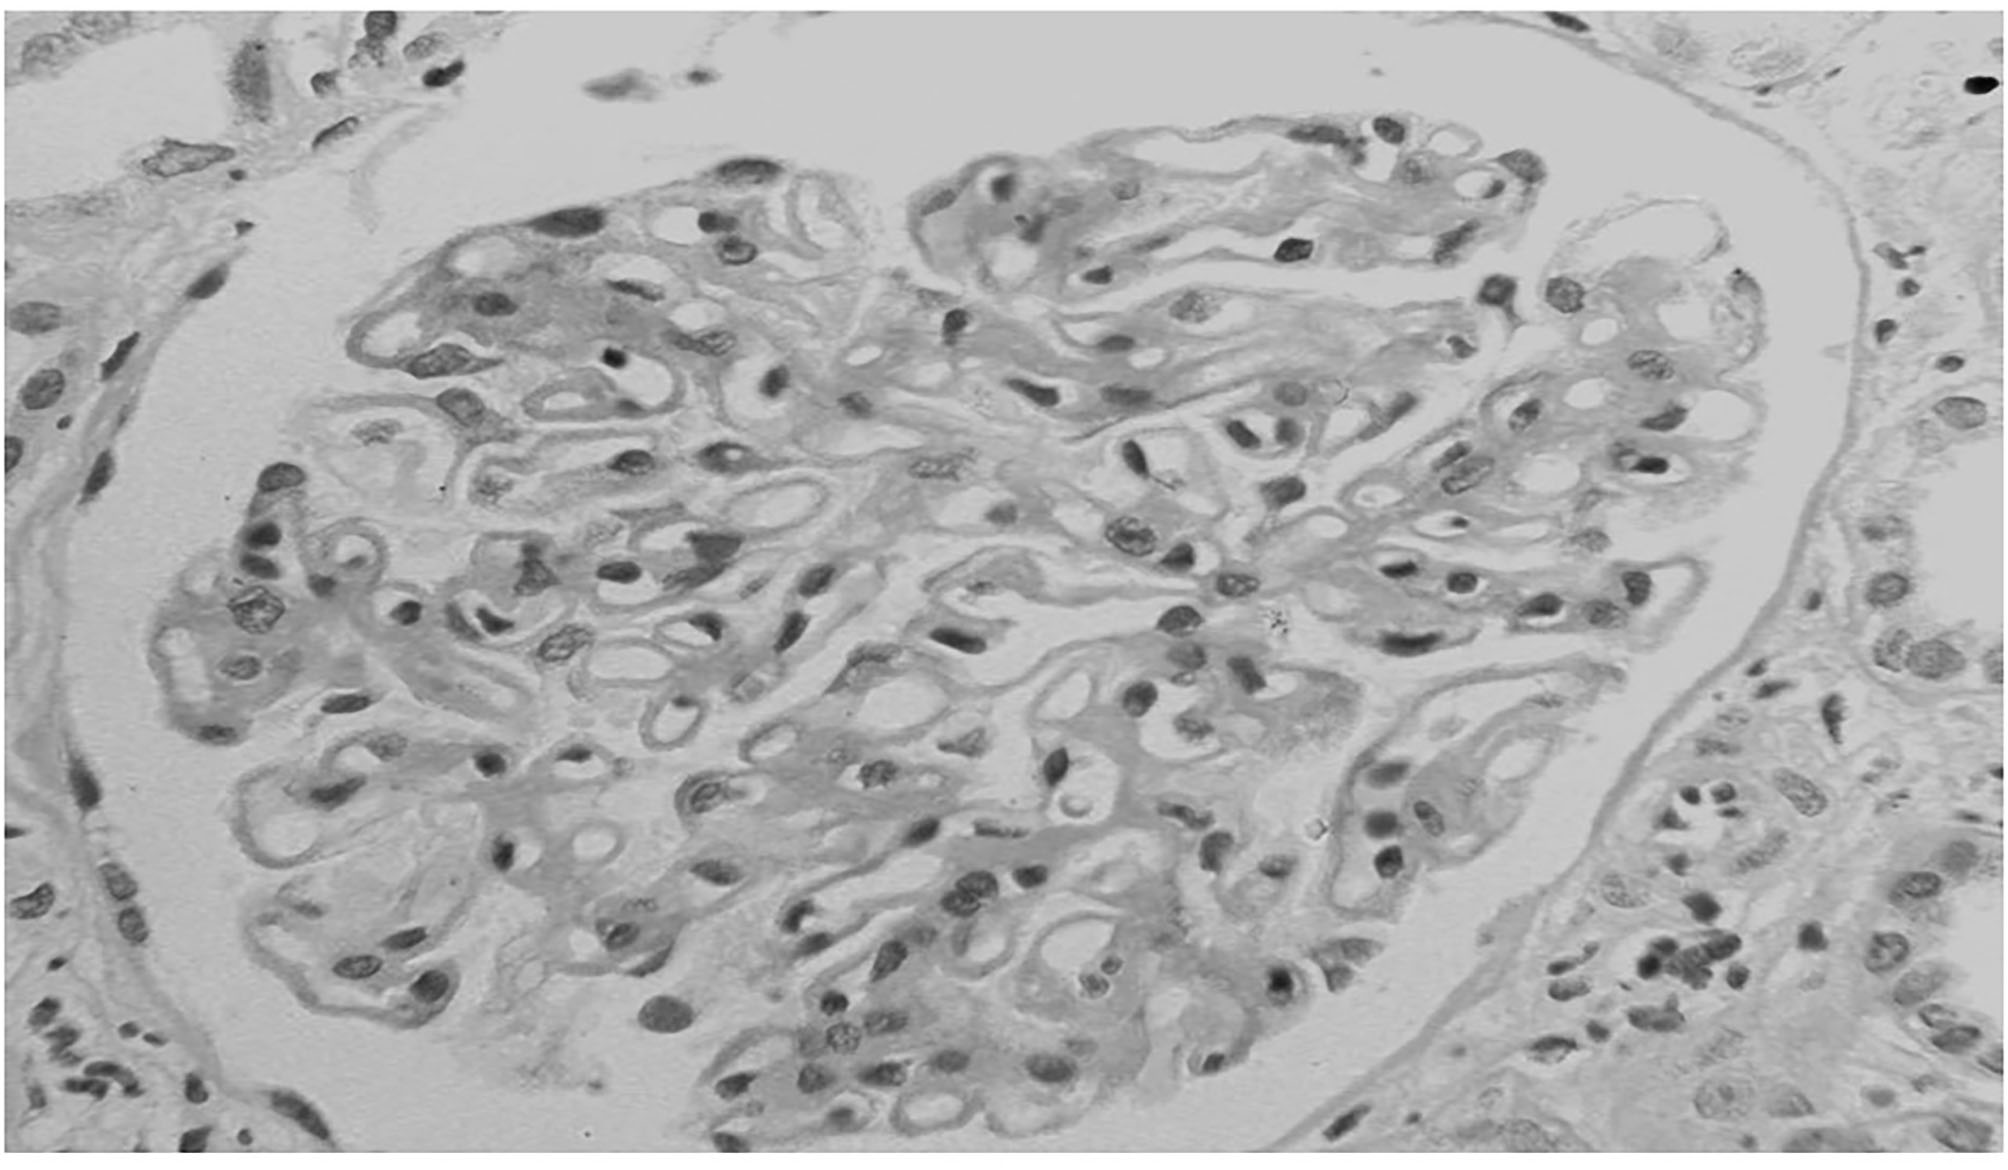

Figure 2

Membranous nephropathy in a patient with lung cancer. At light microscopy together with the diffuse thickening of glomerular capillary walls, some infiltration of leukocytes is present in capillary lumens.